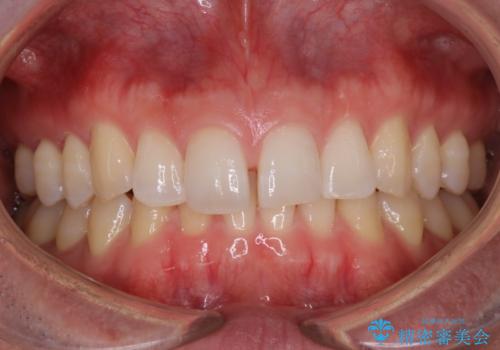

【非抜歯】インビザラインで正しい噛み合わせを

【非抜歯】インビザラインでガタつきと口元を改善!非抜歯でも印象が変わる矯正治療